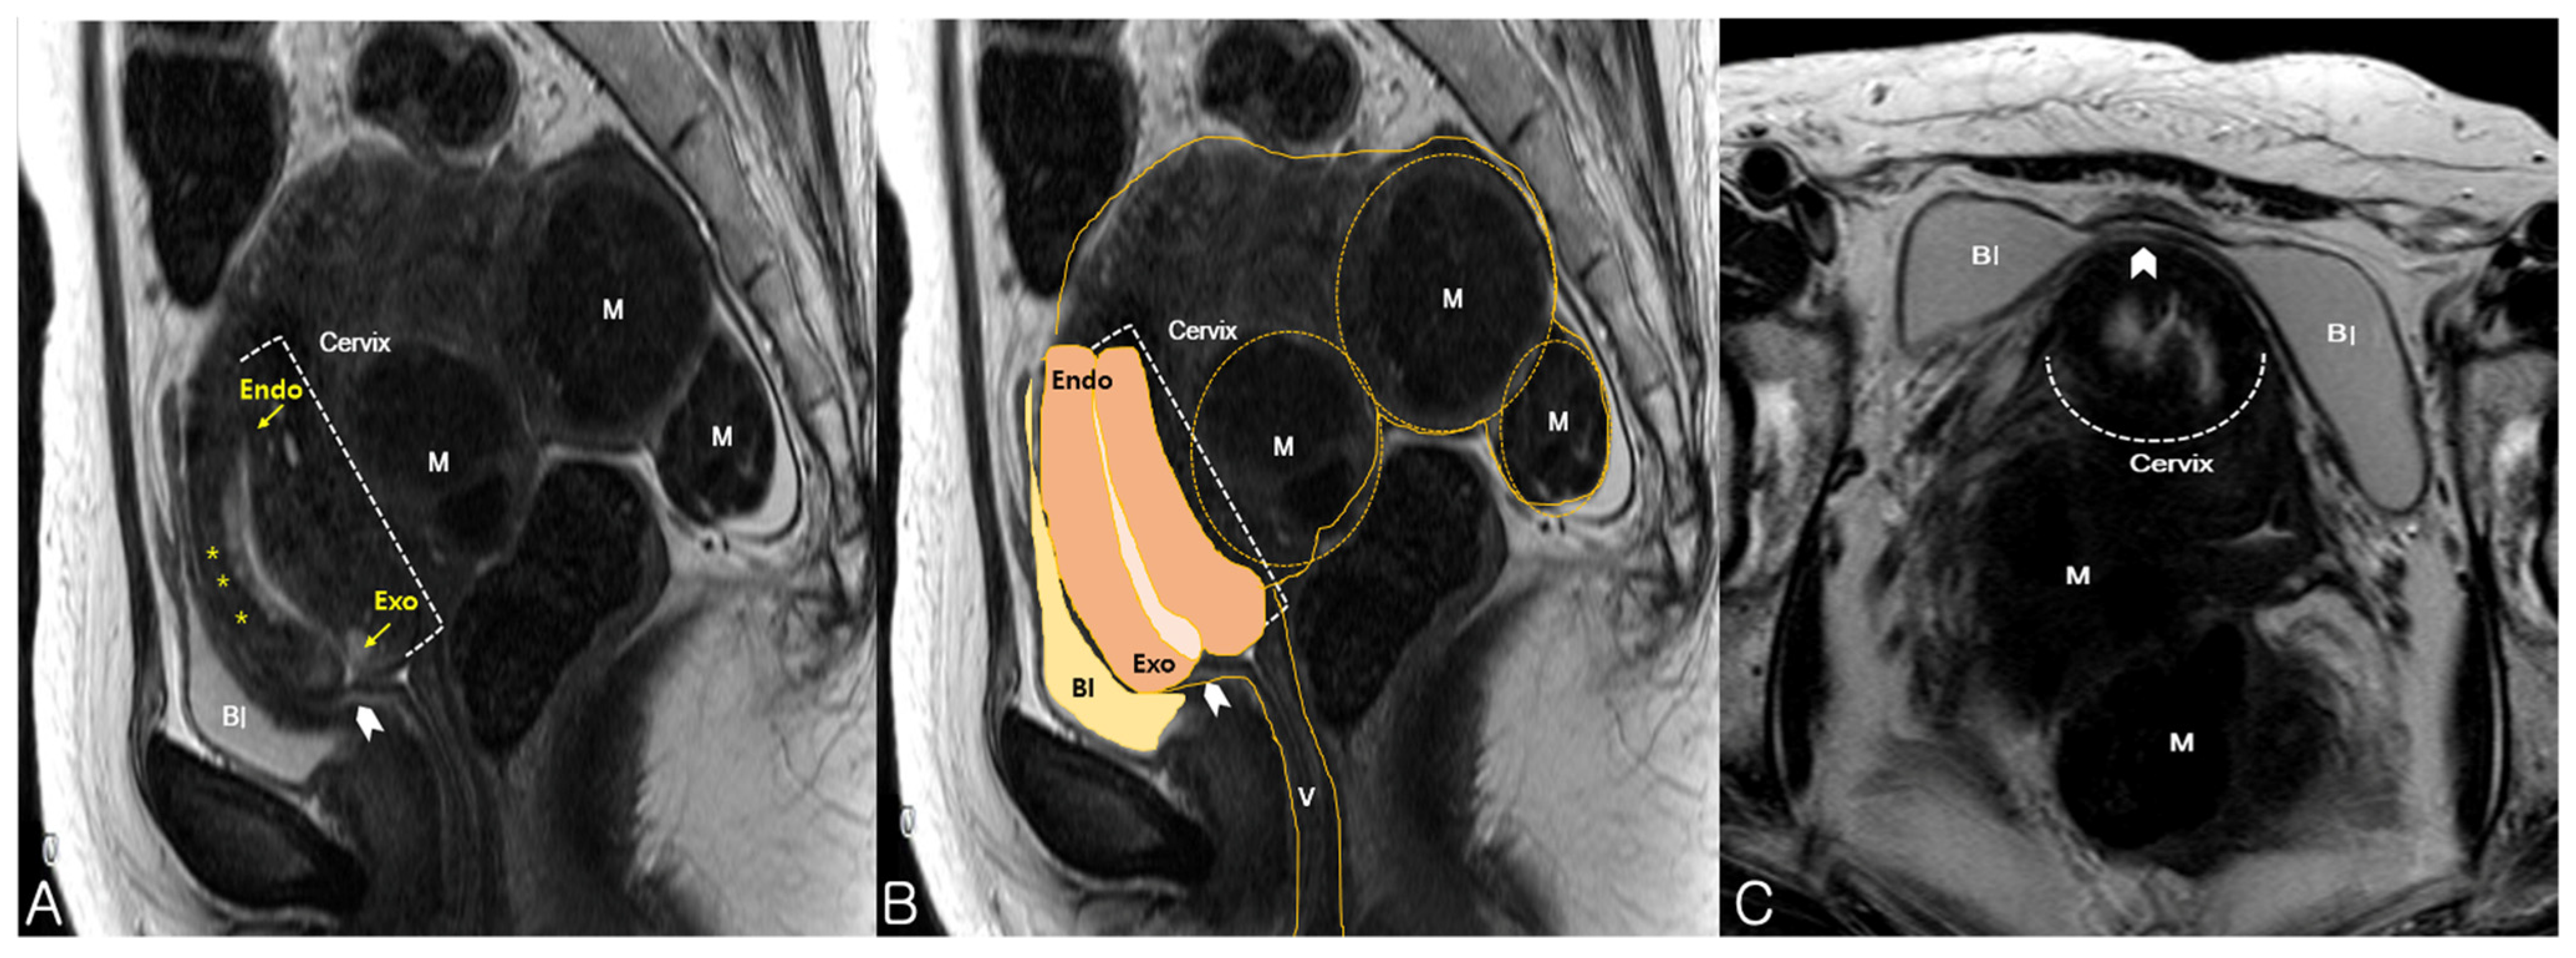

2. Case Presentation